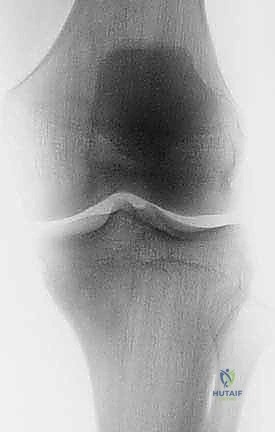

لفهم مدى تعقيد وعبقرية جراحة استئصال الظنبوب القريب، من الضروري الإبحار في أعماق التشريح الأساسي لهذه المنطقة الحيوية. لا يقتصر الأمر على مجرد عظام، بل هو نظام هندسي وبيولوجي متكامل ومعقد. يتكون مفصل الركبة من التقاء عظم الفخذ (Femur) من الأعلى، وعظم الساق أو الظنبوب (Tibia) من الأسفل، وعظم الشظية (Fibula) الجانبي، بالإضافة إلى الرضفة أو صابونة الركبة (Patella) في الأمام. الجزء القريب من الظنبوب هو الجزء العلوي العريض من عظم الساق، والذي يشكل القاعدة الأساسية التي يستند عليها مفصل الركبة ويتحمل وزن الجسم بأكمله.

في حالات نادرة، قد لا يكون السبب ورماً، بل صدمة شديدة (مثل حوادث السير المروعة) التي تؤدي إلى تهشم كامل للجزء القريب من الظنبوب مع فقدان عظمي ضخم لا يمكن إصلاحه بالشرائح والمسامير. كذلك، في حالات الفشل المتكرر والالتهابات المزمنة لعمليات تغيير مفصل الركبة التقليدية (Revision Total Knee Arthroplasty) والتي تؤدي إلى ذوبان وفقدان عظمي كبير، يكون الحل النهائي هو استخدام الأطراف الصناعية الضخمة (Megaprosthesis) لتعويض هذا النقص الهائل.